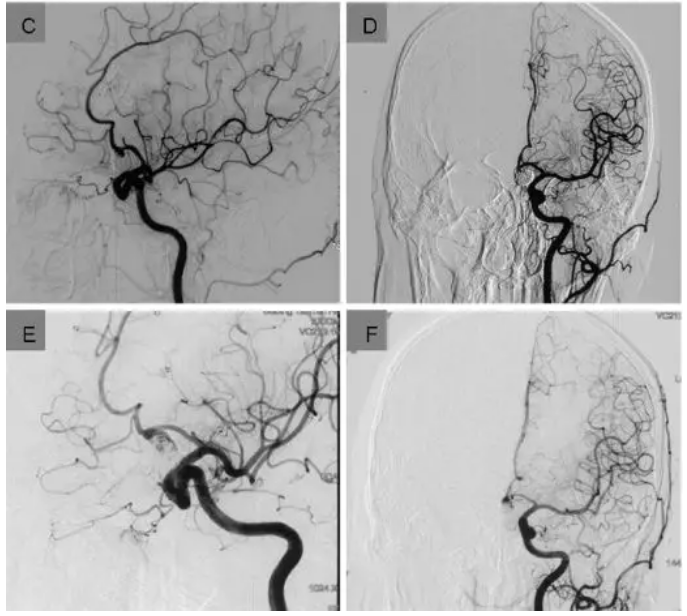

图二:如图所示是一个62岁的女性未破裂动脉瘤患者。动脉瘤位于前交通动脉(A-B);经介入治疗后,可见动脉瘤完全闭塞(C-D);术后9个月,病人逐渐出现视力障碍,复查DSA可见动脉瘤复发(E-F)。